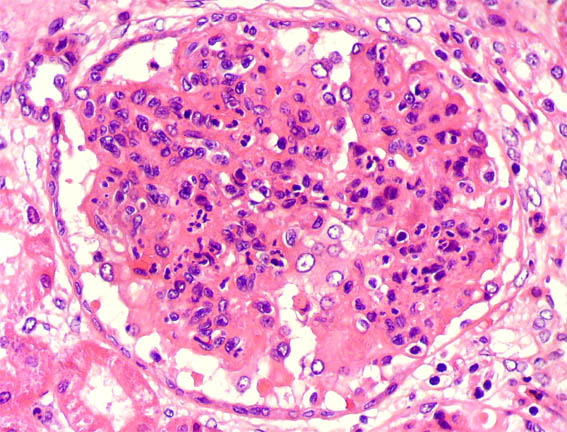

Examine the renal histopathology slide. What is the probable diagnosis?

Explanation: ***Post-streptococcal glomerulonephritis*** - Characterized by **diffuse endocapillary hypercellularity** with **neutrophil infiltration** and enlarged, hypercellular glomeruli on light microscopy. - Electron microscopy shows pathognomonic **subepithelial electron-dense deposits** (humps), and immunofluorescence reveals a **starry sky pattern** with granular C3 and IgG deposits. *Membranoproliferative GN* - Shows **mesangial proliferation** with **double contour** appearance of glomerular basement membrane on light microscopy. - Electron microscopy reveals **subendothelial deposits** and **mesangial interposition**, not subepithelial humps. *Rapidly progressive GN* - Histologically characterized by **crescents** (>50% of glomeruli) composed of proliferating **epithelial cells** and **macrophages**. - Shows **necrotizing glomerulonephritis** with **fibrinoid necrosis** and **segmental sclerosis**, not endocapillary hypercellularity. *Diabetic nephropathy* - Light microscopy shows **nodular glomerulosclerosis** (Kimmelstiel-Wilson nodules) and **diffuse mesangial expansion**. - Electron microscopy reveals **thickened glomerular basement membrane** and **mesangial matrix expansion**, without immune deposits.